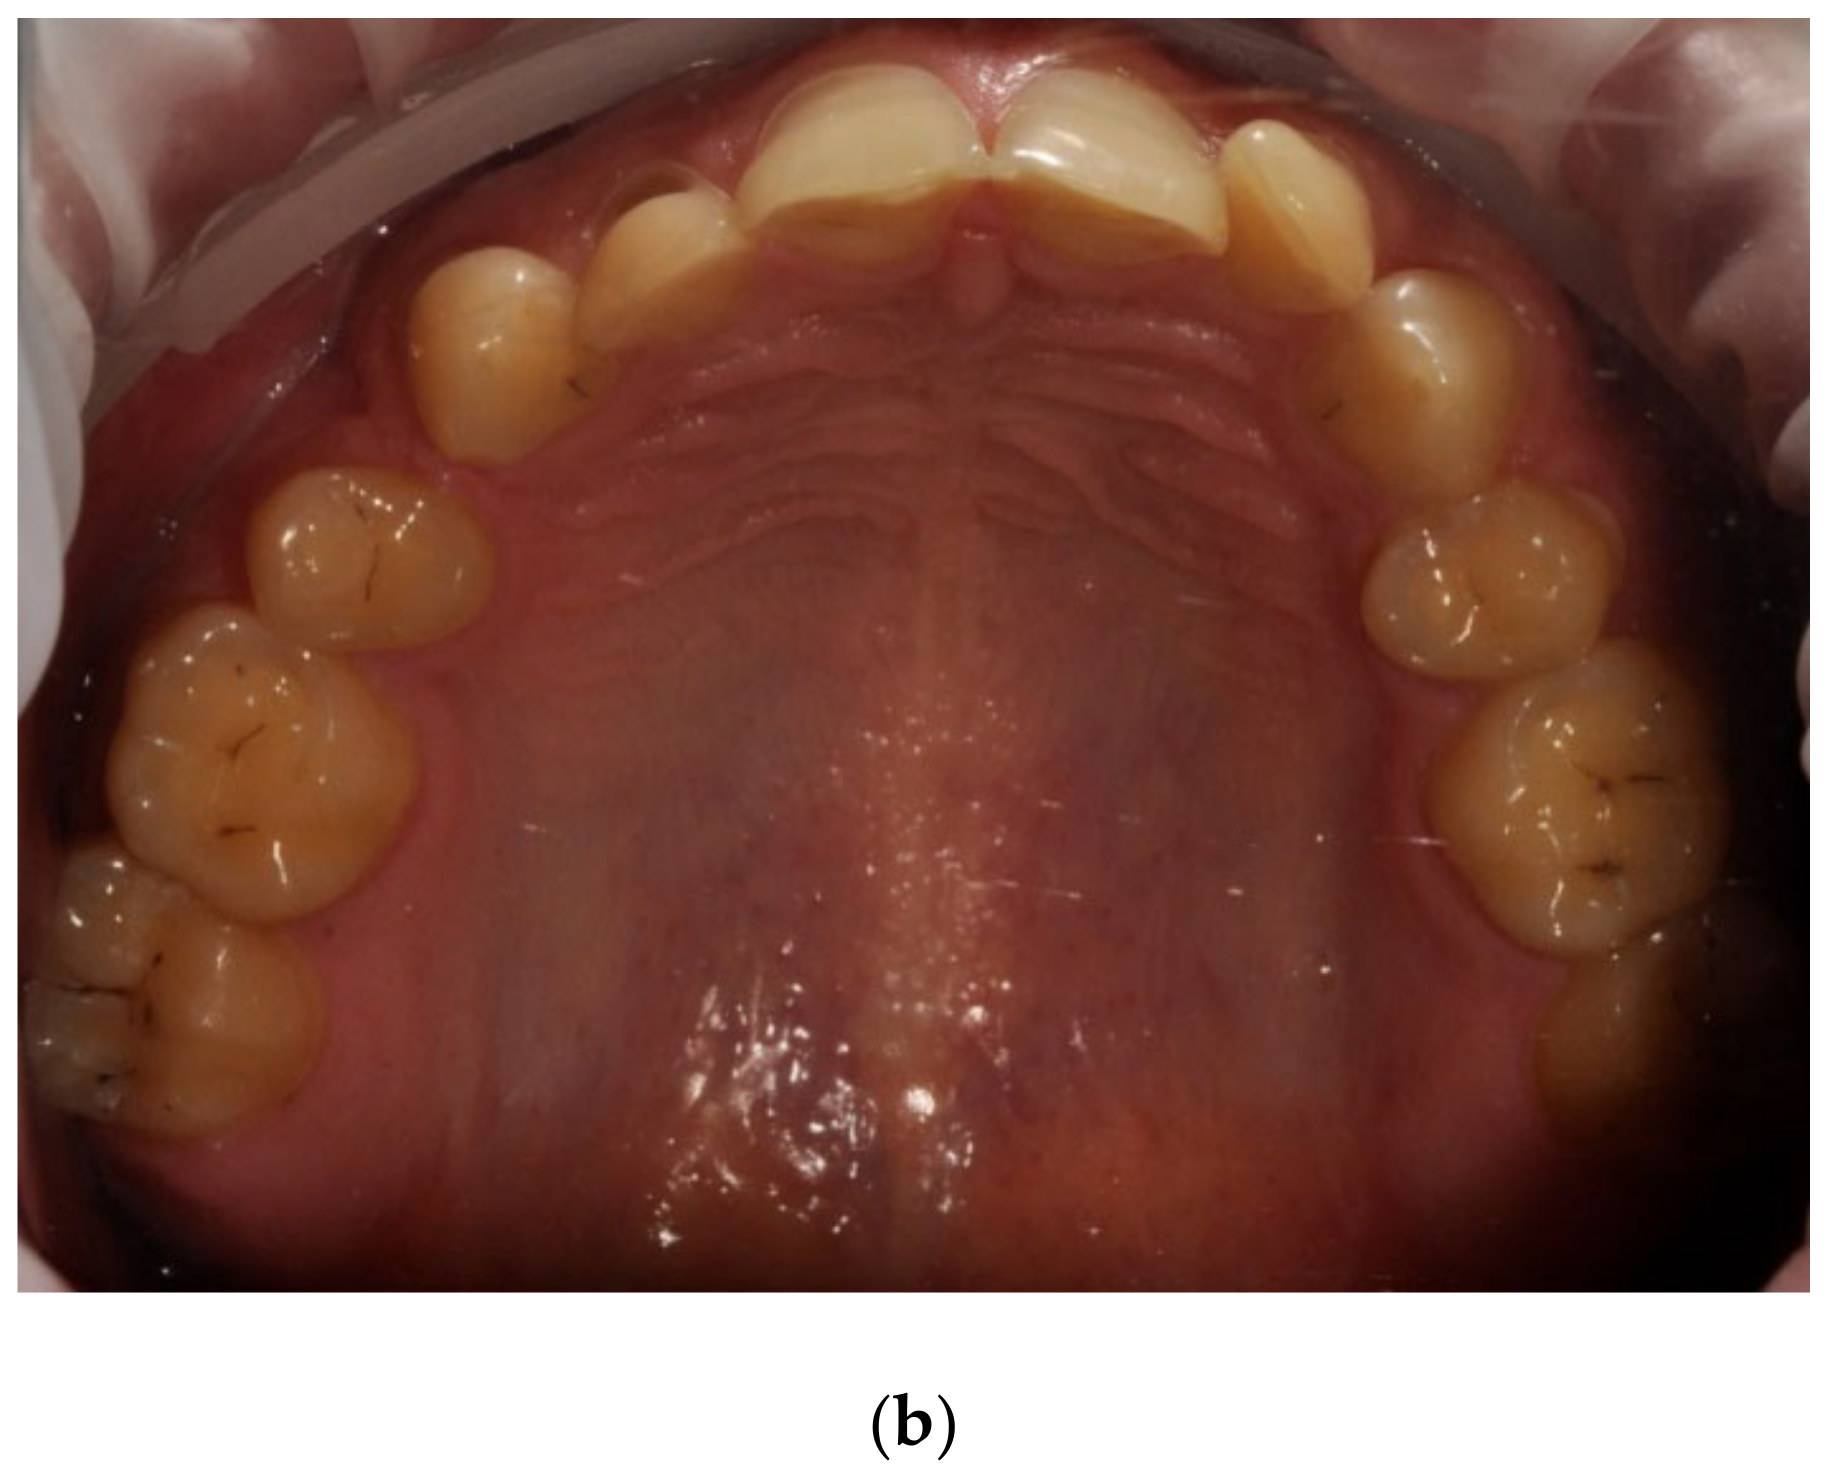

The mean API score among the subjects was 63.47% (SD = 22.78) and ranged between 22 and 100%. The mean value of the index for the control group was 68.75% (SD 21.46) and ranged from 19 to 100%. The p > 0.05, therefore the study and control groups did not differ significantly from the API value. The median value of the API index for the study group was 65 and 68.5 for the control group. Table 3 and Figure 1 present the API score and the API score pictured according to interpretation values. Figure 2, Figure 3 and Figure 4 show the clinical situation of the participants. The API values did not have a normal distribution in the analyzed groups (p < 0.05 from the Shapiro–Wilk test), so the analysis was carried out using the Mann–Whitney test.

Figure 4. Man, 42 y.o. API = 100%. The patient refused to use professional oral hygiene products and used soap to brush his teeth. Dental plaque deposits. Dental Biofilm-induced Gingivitis.